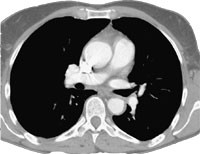

Røntgen thorax viste venstresidig pleuraadheranse. Ultralydundersøking av venstre underekstremitet viste trombe i v. femoralis communis med proksimal grense i v. iliaca externa. Pulmonal angiografi viste ein stor embolus i overgangen mellom greinene til venstre underlapp og lingula, utan kontrastfylling av segmentgreinene til øvre del av underlappen (fig 3). I samme seanse blei det utført kateterdirigert, lokal trombolyse (tab 1).

Ved kontroll dagen etter var det ein liten resttrombe i arterien til venstre underlapp, men det meste av tromben var lysert. Segmentgreinene til underlappen var opne (fig 4). Behandlinga blei avslutta. Ultralydundersøking tre dagar etterpå viste at tromben i v. iliaca externa og v. femoralis communis sinistra var borte.